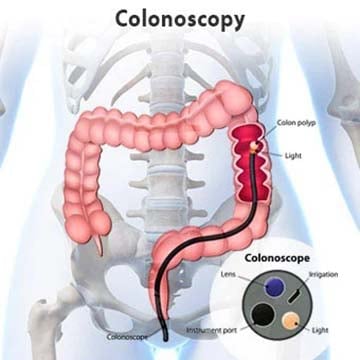

کولونوسکوپی یعنی چه؟

کولونوسکوپی آزمایشیه که برای تشخیص تغییرات یا موارد غیر عادی در روده بزرگ و رکتوم ( راست روده ) مورد استفاده قرار می گیره. کولونوسکوپی یکی از روش های شایع برای تشخیص و نمونه برداری پولیپ هاست.

کولونوسکوپی چطوری انجام می شه؟

در طول کولونوسکوپی یک لوله طولانی و انعطاف پذیر در رکتوم ( راست روده) قرار داده می شه. یک دوربین ویدئویی کوچک در بالای لوله وجود دارد که به پزشک اجازه می دهد تا داخل کل روده بزرگ را به خوبی مشاهده کند. در طول کولونوسکوپی، اگر نیاز باشد، پولیپیا سایر بافت های غیر طبیعی را می توان حذف کرد. در طول کولونوسکوپی نیز می توان بافت های نمونه ( بیوپسی) را برداشت.

پزشک یک کولونوسکوپ را در داخل رکتوم شما قرار می دهد. اسکوپ ( که به اندازه روده شما طولانی است) شامل یک چراغ و یک لوله است که به پزشک اجازه می دهد هوا را به داخل روده ی بزرگ پمپ کند. هوا باعث باد شدن روده می شود و همین امر به پزشک اجازه می دهد مسیر روده را به خوبی مشاهده کند. زمانی که اسکوپ حرکت داده می شود یا هوا به داخل آن دمیده می شود، ممکن است درد شکم و یا احساس اجابت مزاج داشته باشید. کولونوسکوپ حاوی یک دوربین ویدئویی کوچک است. دوربین، تصاویر حاصل را به یک مانیتور خارجی ارسال می کند بنابراین پزشک می تواند داخل روده را به خوبی مشاهده کند. پزشک می تواند ابزاری را در کانال (لوله) قرار دهد تا بتواند نمونه ای از بافت ها را بردارد و یا اینکه پلیپ ها وسایر بافت های غیر عادی را حذف کند. کولونوسکوپی معمولا ۲۰ دقیقه تا یک ساعت طول می کشد.